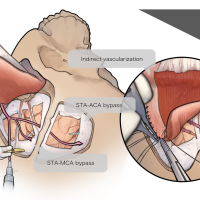

術後イラストシリーズ